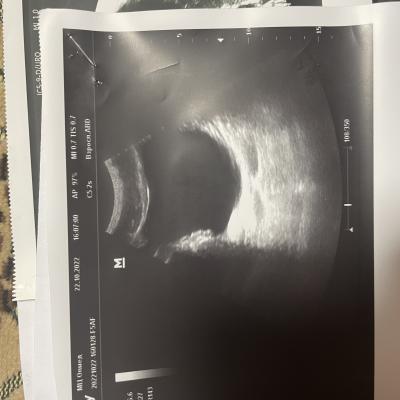

Здравствуйте, болят яички 1.5 года. 6 месяцев режет при мочеиспускании, боли в копчике (начинается с копчика, в течение дня усиливаются, поднимаются выше боли). Может ли это быть из-за мочевого пузыря? Фото прикрепил, там есть образование некое. Бак посев мочи отриц, эр, лейк. в норме, зппп отриц, в секрете простаты клебсиела, кровь в норме, млча в норма. Мрт поясницы делал, невролог сказал, что боли точно не из-за невролгии.

Добрый день! Вам нужно выполнить МРТ малого таза - там будет видно образование в стенке мочевого пузыря (если оно действительно есть). После этого надо обратиться к онкоурологу для интерпретации результатов МРТ и решения вопроса о дальнейшей тактике. Удачи.